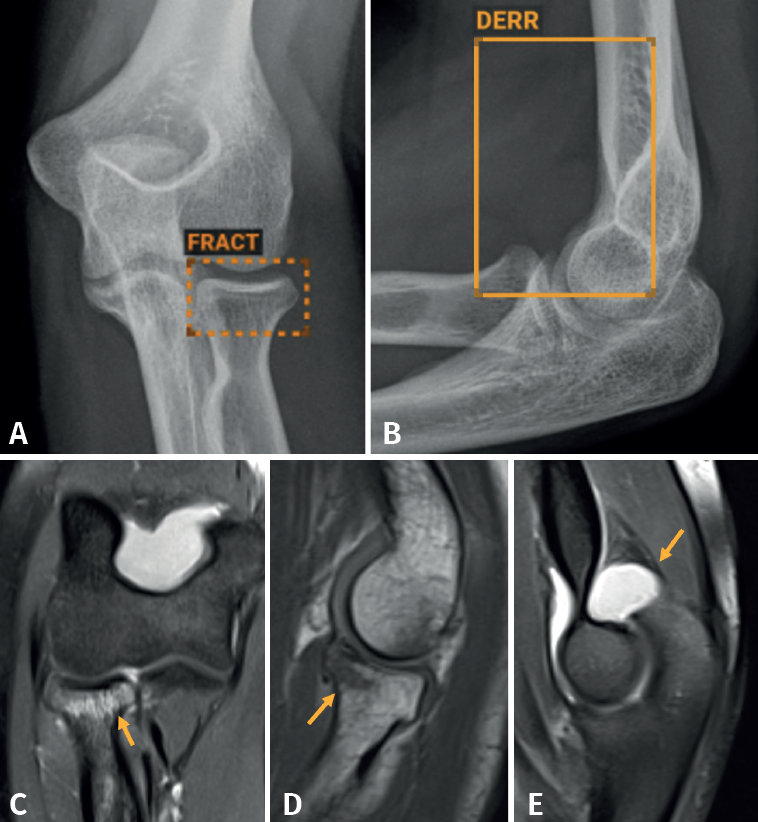

En nuestro caso, decidimos que toda radiografía que llega al PACS se enviara directamente y de manera automática al análisis por la IA, evitando un uso “a demanda” del médico, para favorecer su consulta. El resultado del análisis es devuelto al PACS en un plazo de 1-2 minutos, poniéndolo a disposición del personal médico para su valoración. Los resultados se presentan de manera clara y fácil de interpretar, en 3 niveles: negativo, dudoso o positivo (Figura 2); los dos últimos señalan con un recuadro en la radiografía la imagen de fractura. La diferencia entre un resultado positivo (recuadro con línea continua) y uno dudoso (recuadro con línea discontinua) estriba en un nivel de confianza alto o intermedio para la lesión detectada. Esta solución de IA detecta fracturas en todas las localizaciones anatómicas excepto el cráneo y la columna cervical, y, además, identifica derrames articulares, luxaciones y lesiones óseas. Como control de calidad, se indica el número de imágenes recibidas y el número de imágenes analizadas.

Aunque no hemos realizado un estudio de sensibilidad y especificidad por la complejidad que entraña en la práctica asistencial, consideramos que los resultados son satisfactorios, en línea con lo publicado en la literatura científica. Destacamos la eficacia del algoritmo en la detección de pequeñas fracturas arrancamiento (Figura 3), fracturas de radio distal y proximal (Figura 4), y fracturas múltiples (Figura 5).